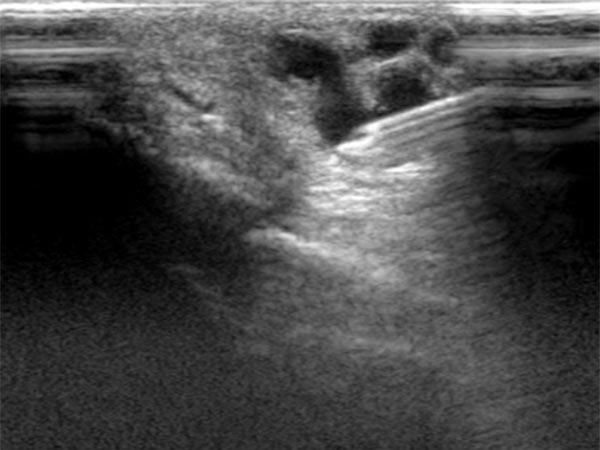

Im Ultraschall imponiert subkutan epifaszial am dritten Finger eine dilatierte Drainagevene aus der digitalen AVM. In der Farbduplexsonographie (FKDS) bestätigt sich der fast-flow arterio-venöse Shunt mit hohem Durchfluss.

Nachdem es technisch nicht möglich ist, die AVM zur Re-Embolisation nur von transarteriell zu behandeln, wird sonographisch gesteuert nun der perkutane Behandlungsweg in Direktpunktionstechnik gewählt.

Perkutanes, sonograhisch gesteuertes Vorschieben der Punktionsnadel in die Drainagevene der digitalen AVM.